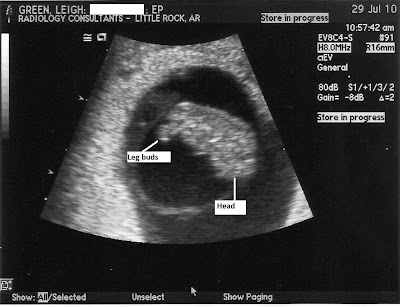

Anyway, I took Brady to school and immediately called the nurse this morning. As I explained to her what was going on she suggested I just come on in for an ultrasound. I jumped at the chance for another look inside the belly. Our sweet ultrasound technician, Elizabeth, was nervous that we were back to see her so soon. Her first view of baby showed an obvious heartbeat. What a relief!! And it was beating at 171...way up from the 120 two weeks ago. Then she commented that we had ourselves a little gummy bear in there. The pictures below will show you what she meant. The baby has limb buds right now instead of arms and legs and really does resemble a gummy bear. :) The baby is measuring right on track from two weeks ago.